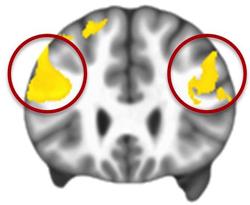

In this MRI data composite, the yellow indicates the prefrontal cortex areas that are significantly underactive in people with autism while regulating their emotions. Image courtesy of Gabriel Dichter, Ph.D., UNC School of Medicine.

The brain scans of people with autism were different. "The prefrontal cortex did not come online to the same extent," Dichter said. "It was as though the brain region that's needed to work hard to regulate emotional responses couldn't activate to the same degree as it did in people without autism. This limited activation of the prefrontal cortex, not surprisingly, resulted in less modulation of the limbic regions."

Thus, when faced with emotional situations, people with autism do not use their prefrontal cortices to regulate emotions to the same extent as people without autism. This in turn may lead to the "associated symptoms," such as anxiety, tantrums, and irritability, which can be pervasive.